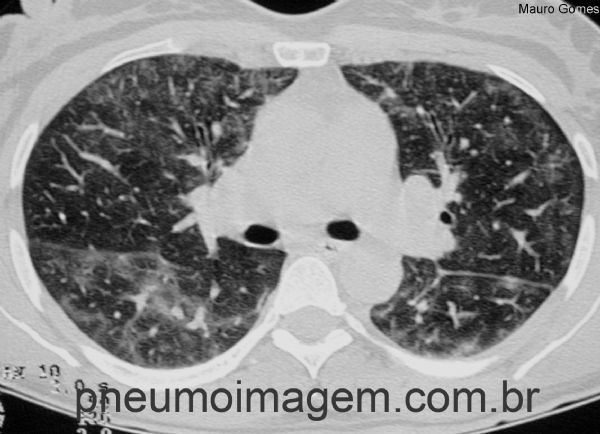

Corte tomográfico em alta resolução (TCAR) com opacidades irregulares em vidro fosco difusas e bilaterais.

High resolution tomographic (HRCT) slices with irregular diffuse and bilateral ground glass opacities.